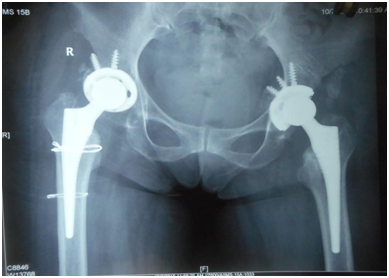

Because knee surgery requires deep flexion at hip, we decided to replace hips first. Patient was given general anesthesia, put in lateral position, and operated using posterior approach. Because head was not dislocatable, in situ neck osteotomy had to be done and then acetabulum was reamed through the ankylosed head taking care of the acetabular walls and positioning. Extensive soft tissue releases were required to correct the deformities and a primary non-constrained uncemented implant was used (Stryker). Figure 5 owing to the osteoporotic bone, there was undisplaced spiral fracture of right proximal femur which was taken care of using cerclage wires. Adductor tenotomy was done postoperatively as the tendons standout only after taking down the ankylosis.

Figure 5 Postoperative radiograph showing bilateral total hip.